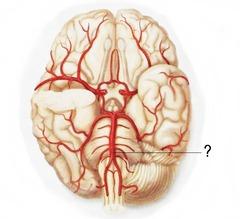

Basilar artery

Circle of Willis

Internal/external/common carotid artery

Vertebral artery